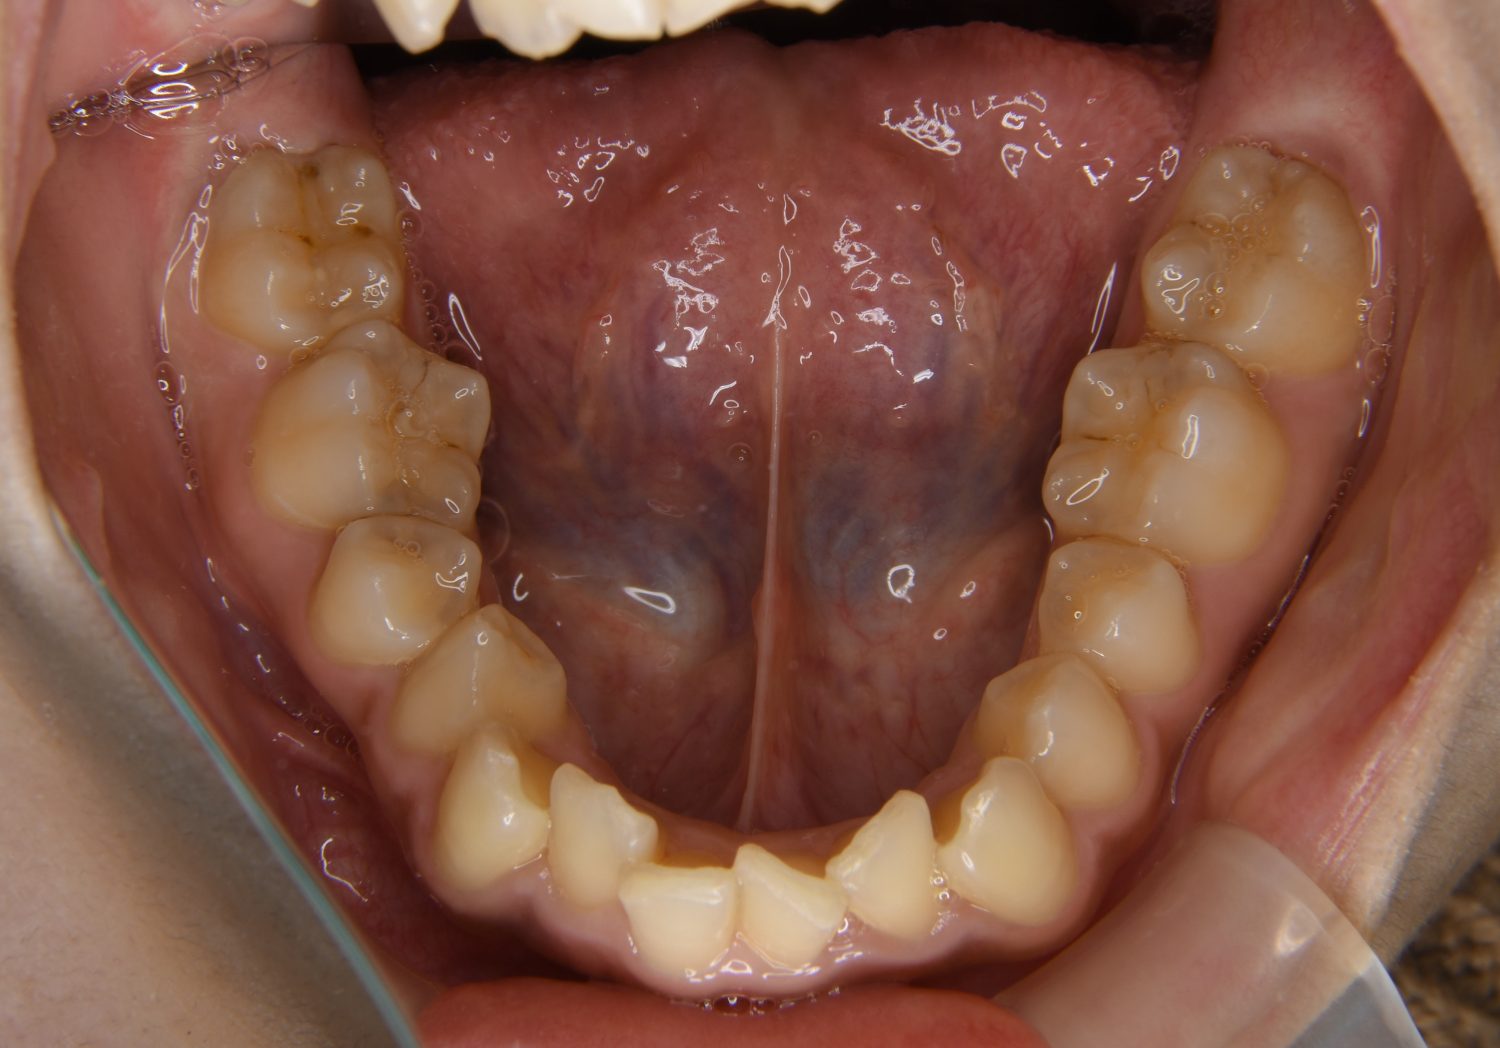

叢生の症例紹介②

Before

After

主訴

歯の凸凹を治したい。

治療内容

アライナー(インビザライン)にて非抜歯で治療を行いました。

治療費

1,150,000 円(税込)

治療期間

26ヶ月

通院回数

14回

想定されたリスク

※歯根吸収、歯肉退縮、歯髄壊死、顎関節症状

※アライナー(インビザライン)は日本の薬機法未承認の矯正装置であり、医薬品副作用被害救済制度の対象外となる場合があります。

丸山和宏先生

ピーススマイル矯正歯科

上下前歯部に叢生(凸凹)が認められる状態でした。歯列の遠心移動を行うことで機能面および審美面が改善されました。